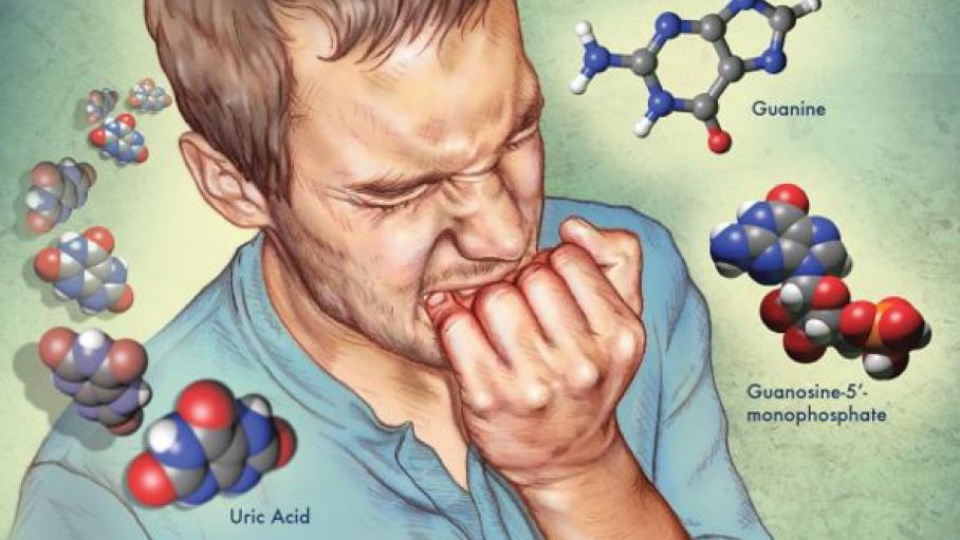

قیمت: 45٬000 تومان - دسته بندی فایل: پاورپوینتدانلود پاورپوینت آشنایی با سندروم نشانگان لش نیهان

خرید پاورپوینت حرفه ای با موضوع آشنایی با سندروم نشانگان لش نیهان با قیمت استثنایی از لوکس فایل